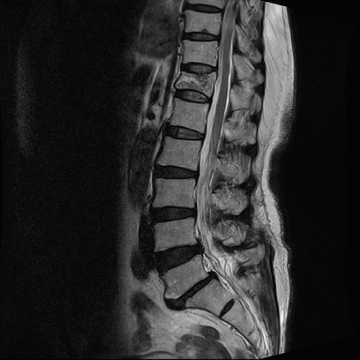

척추뼈가 외부 충격으로 인해 찌그러지고 골절되는 질환입니다.

척추뼈의 경우 팔과 다리뼈의 골절과는 다르게 뼈가 찌그러지듯이 납작해지기 때문에 '압박골절'이라 표현합니다. 외형상 변화가 없이 때문에 발생된 후에도 잘 느끼지 못한 채 방치하는 경우가 많습니다.

압박 골절된 척추뼈 (2016.03.18)